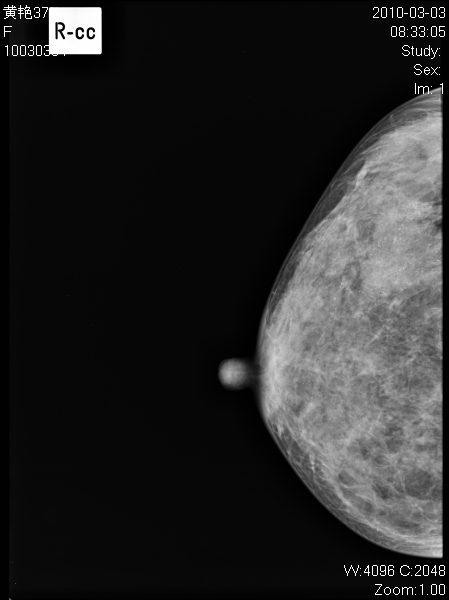

以下是引用子期在2010-3-23 8:29:00的发言:[br]右乳肿块,边缘毛糙,内见砂砾状钙化,考虑乳癌。[br]少了一张片啊。

以下是引用拾荒者在2010-3-23 20:04:00的发言:[br]右乳肿块,边缘毛糙,境界不清,内见多发砂砾状钙化,考虑浸润性导管癌可能。

以下是引用37度在2010-3-24 11:00:00的发言:[br]右乳肿块,边缘毛糙,内见砂砾状钙化,考虑乳癌。